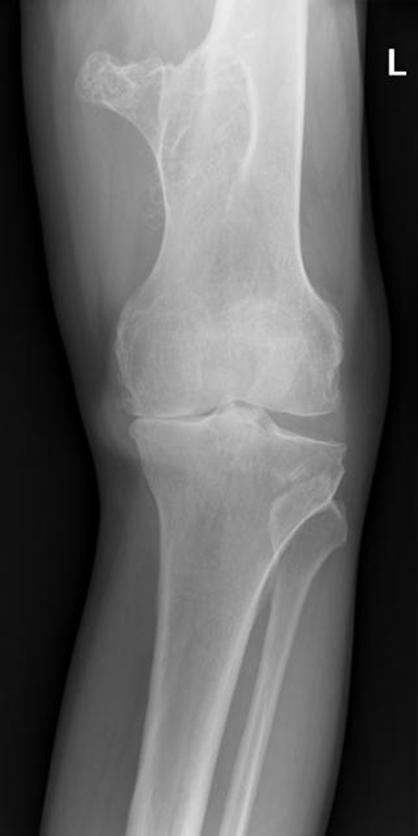

Osteoarthritis

(Degenerative Joint Disease)

Generalized disorder pathologically characterized by loss of joint cartilage and reactive new bone formation.

Cause: traumatic, stress to joints

Complications: joint pain, stiffness, trouble using joints for walking, grasping, etc

Radiographic Appearance: irregular narrowing of joint spaces and development of small bony spurs (osteophytes)

•Knee – articular ends become increasingly dense and joint narrowing is asymmetric

•Fingers – affect distal joints, marginal spurs produce well defined bony protuberances (can palpate and see knobby appearance)

•Hip – asymmetric narrowing of joint space (superiorly and laterally)

Technical: Advance Stage – Subtractive disease

•May require slight decrease

Prognosis: Some patients are unaffected by osteoarthritis while others can be severely disabled.

•Joint replacement surgery for some results in the best long-term outcome.